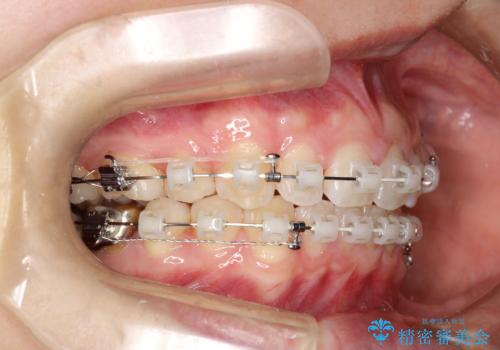

- 矯正装置

- 審美装置

- 治療計画

- 出っ歯を気にして来院されました。

しっかり前歯を下げるために抜歯を合計3本行いワイヤーにて矯正を行う計画としました。